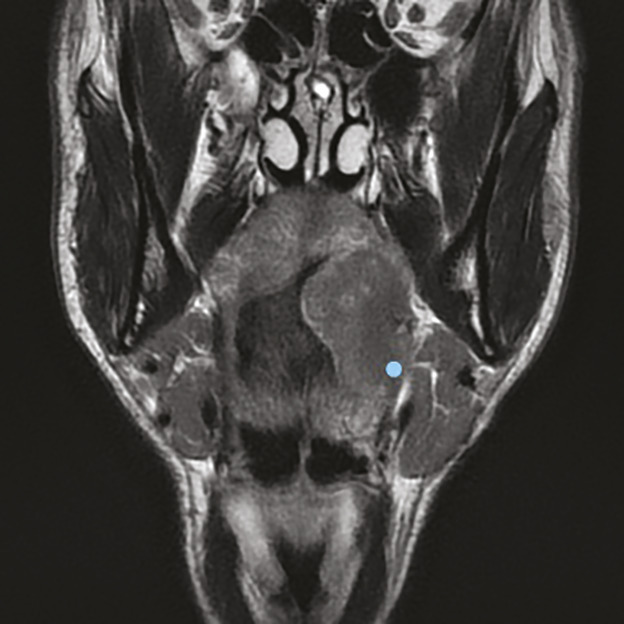

La délimitation entre l’oropharynx et la cavité orale est artificielle, des structures anatomiques pouvant appartenir aux deux localisations. La technique de référence pour l’évaluation tumorale et ganglionnaire est l’IRM cervico-faciale (fig. 2 et 3). Une TDM cervico-faciale peut être réalisée en cas de contre-indication à l’IRM, mais cette technique présente un mauvais contraste tissulaire et ne permet pas d’établir une classification clinique TNM fiable (identification des stades T4). Le scanner facial sans injection permet de chercher une lyse corticale. Une TDM thoracique, voire une TEP-TDM dans les stades avancés, complète le bilan.7